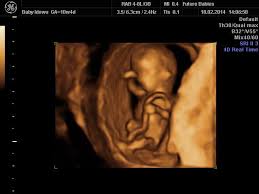

But if you are feeling some uncomfortable symptoms, things may seem like they're dragging. You are 11 weeks exactly pregnant. An ultrasound scan at this stage would show your baby making little, jerky movements. Your 10 weeks pregnant belly. A guide on pregnancy at 10 weeks with information on what to expect, baby development, and symptoms. You are 10 weeks and 2 days pregnant. Meanwhile, your baby is growing and hitting a big milestone at the end of this week. In the 10 weeks pregnant ultrasound, you would notice that your baby's body parts are now visible more clearly.

In the 10 weeks pregnant ultrasound, you would notice that your baby's body parts are now visible more clearly. His toes and fingers have taken a distinct form and started developing fingernails as well. Mar 8, 2021 at 3:14 pm. At 10 weeks, the average fetus is about the size of a strawberry, measuring approximately an inch from crown to rump. You are 11 weeks exactly pregnant. Working arm joints, and 2. Your baby at 10 week pregnant has started developing tissue and you can see his arms and legs forming. Just was told no lifting, no sex, and no other strenuous work until approved by doctor.

At ten weeks pregnant, baby has 1. Check out the illustration below for a look at how things are shaping up inside your belly as you head toward the end of the first trimester. You can have it at 10 weeks of pregnancy or later. Your 10 weeks pregnant belly. Learn about being 10 weeks pregnant.